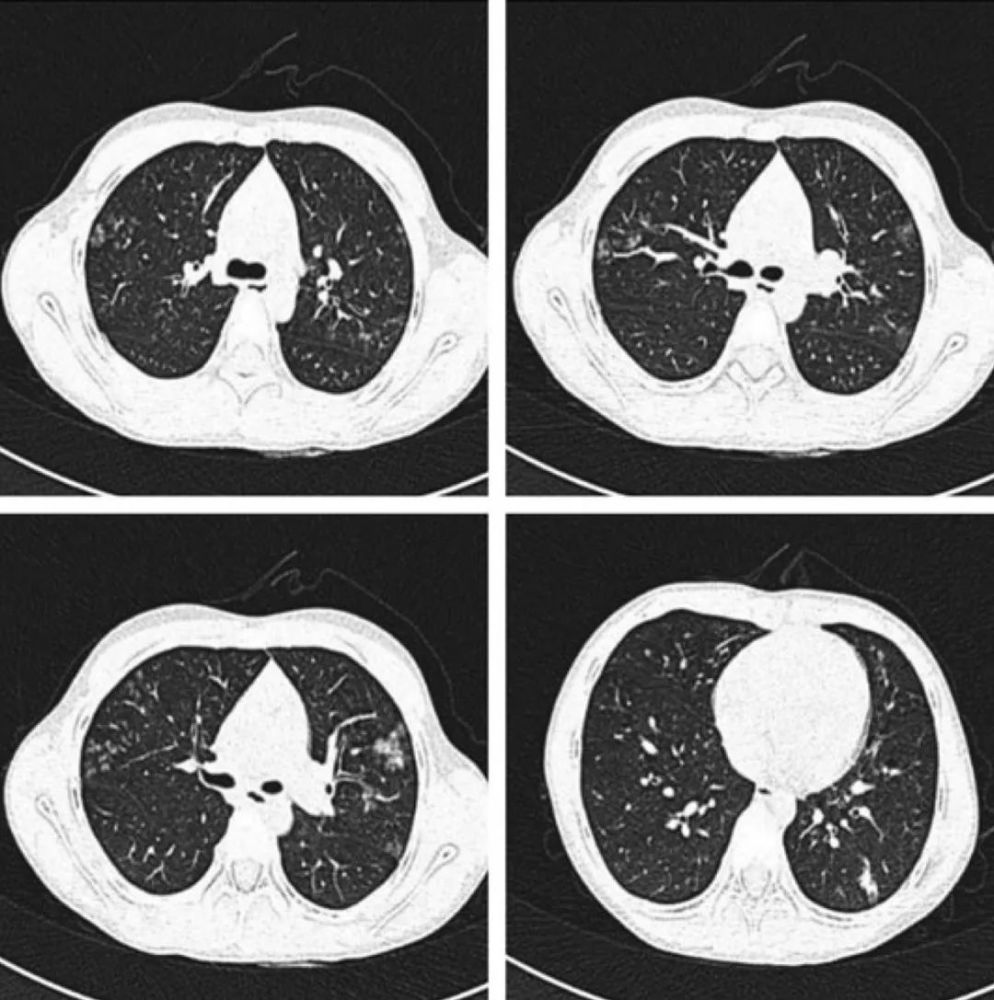

小叶性肺炎CT,大叶性肺炎CT

医学资料,用于学习 小叶性肺炎

小叶性肺炎(支气管肺炎:以支气管为中心的小片状影.

小叶性肺炎

小叶性肺炎ct图片